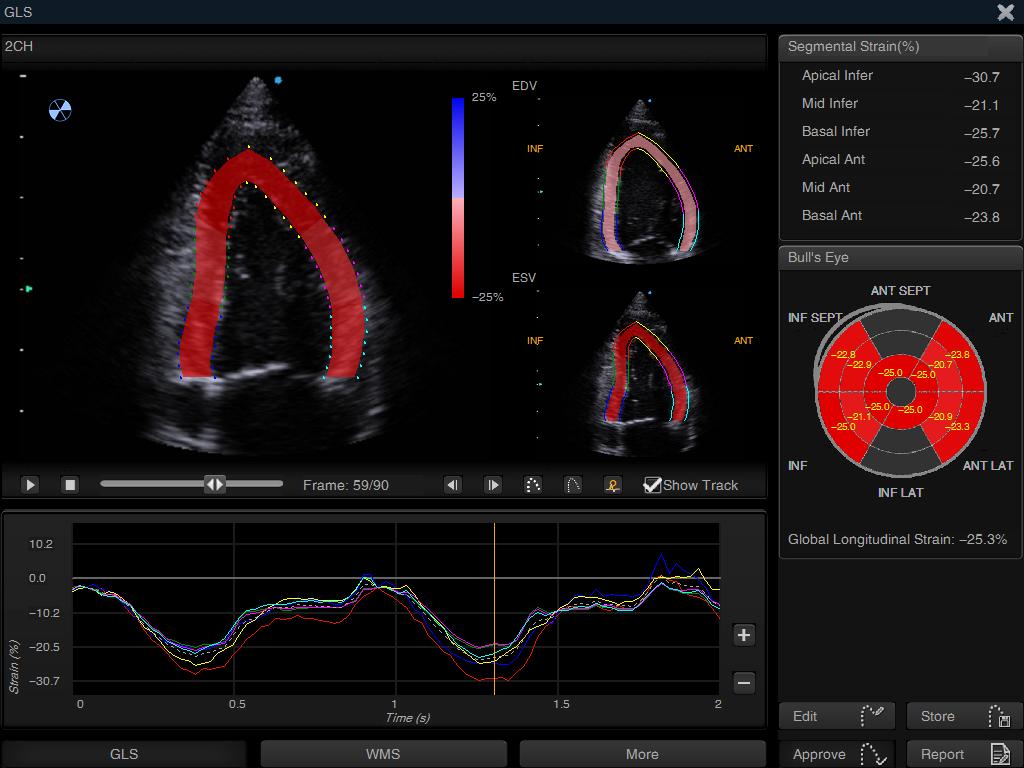

Artificial Intelligence refers to “systems that allow computers or machines to perform or mimic human thinking” (Narang, 2019). AI has been a part of radiology for many years, and anyone with a digital x-ray will be familiar with it. Most of us have also come across AI in cardiac ultrasound, whether it’s the automated calculation of ejection fraction (auto EF) on systems like the Apogee 2300, automated spectral Doppler tracing on the higher end Edan systems, or strain packages on Philips and GE machines.

Above: Strain analysis, automatically performed on the Siui Apogee 2300. This same software package can also generate an ejection fraction automatically, as long as the user is skilled enough to obtain the required two orthogonal views.

Machine learning is a further evolution of AI and allows the computer to continually improve from its ‘experiences’, without explicit instruction from a human. In echocardiography, this usually takes the form of reinforcement learning rather than completely unsupervised learning, with the computer making inferences based on the sonographer’s acceptance or rejection of the computer’s analysis. When performing a strain measurement on the left ventricle, for example, one runs the automated endocardial detection but will frequently adjust one or two points. The current commercially available systems (both on-cart as in the Siui or GE cardiac systems, or offline like Tomtec) do not ‘learn’ anything from this – they employ artificial intelligence, but not machine learning. A system using machine learning would adjust its algorithm based upon the feedback of the user, and improve for next time.